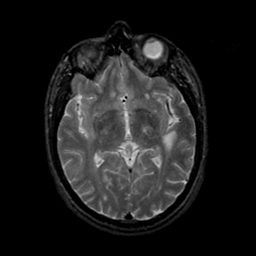

MR Study #9, April 14, 1991 -- Slice #24